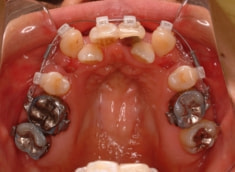

治療開始時

修復歯、補綴歯もあります。下顎8番が水平埋伏しています。